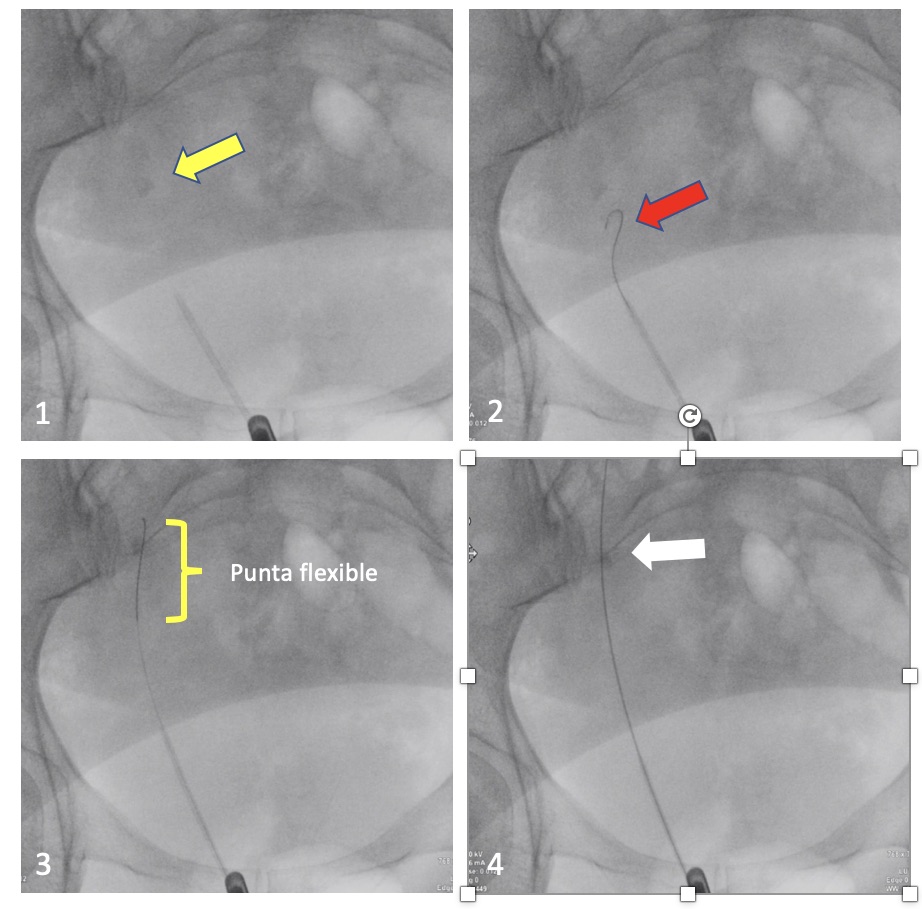

La cirugía se inicia con la instalación de un catéter ureteral externalizado. Éste permite contrastar la vía urinaria superior e identificar en la fluoroscopía, la pelvis y los cálices del riñón a tratar. Posteriormente se realiza una punción renal bajo rayos y/o dirigida por ecografía, hacia la papila renal del cáliz escogido para ingresar. Obtenido este acceso, se avanza una guía hidrofílica y se procede a la dilatación del trayecto percutáneo, lo que permitirá la instalación de una camisa (amplatz) que comunicará la piel con el cáliz y dará acceso al nefroscopio, equipo operado por el urólogo para la fragmentación y extracción de la litiasis a tratar.